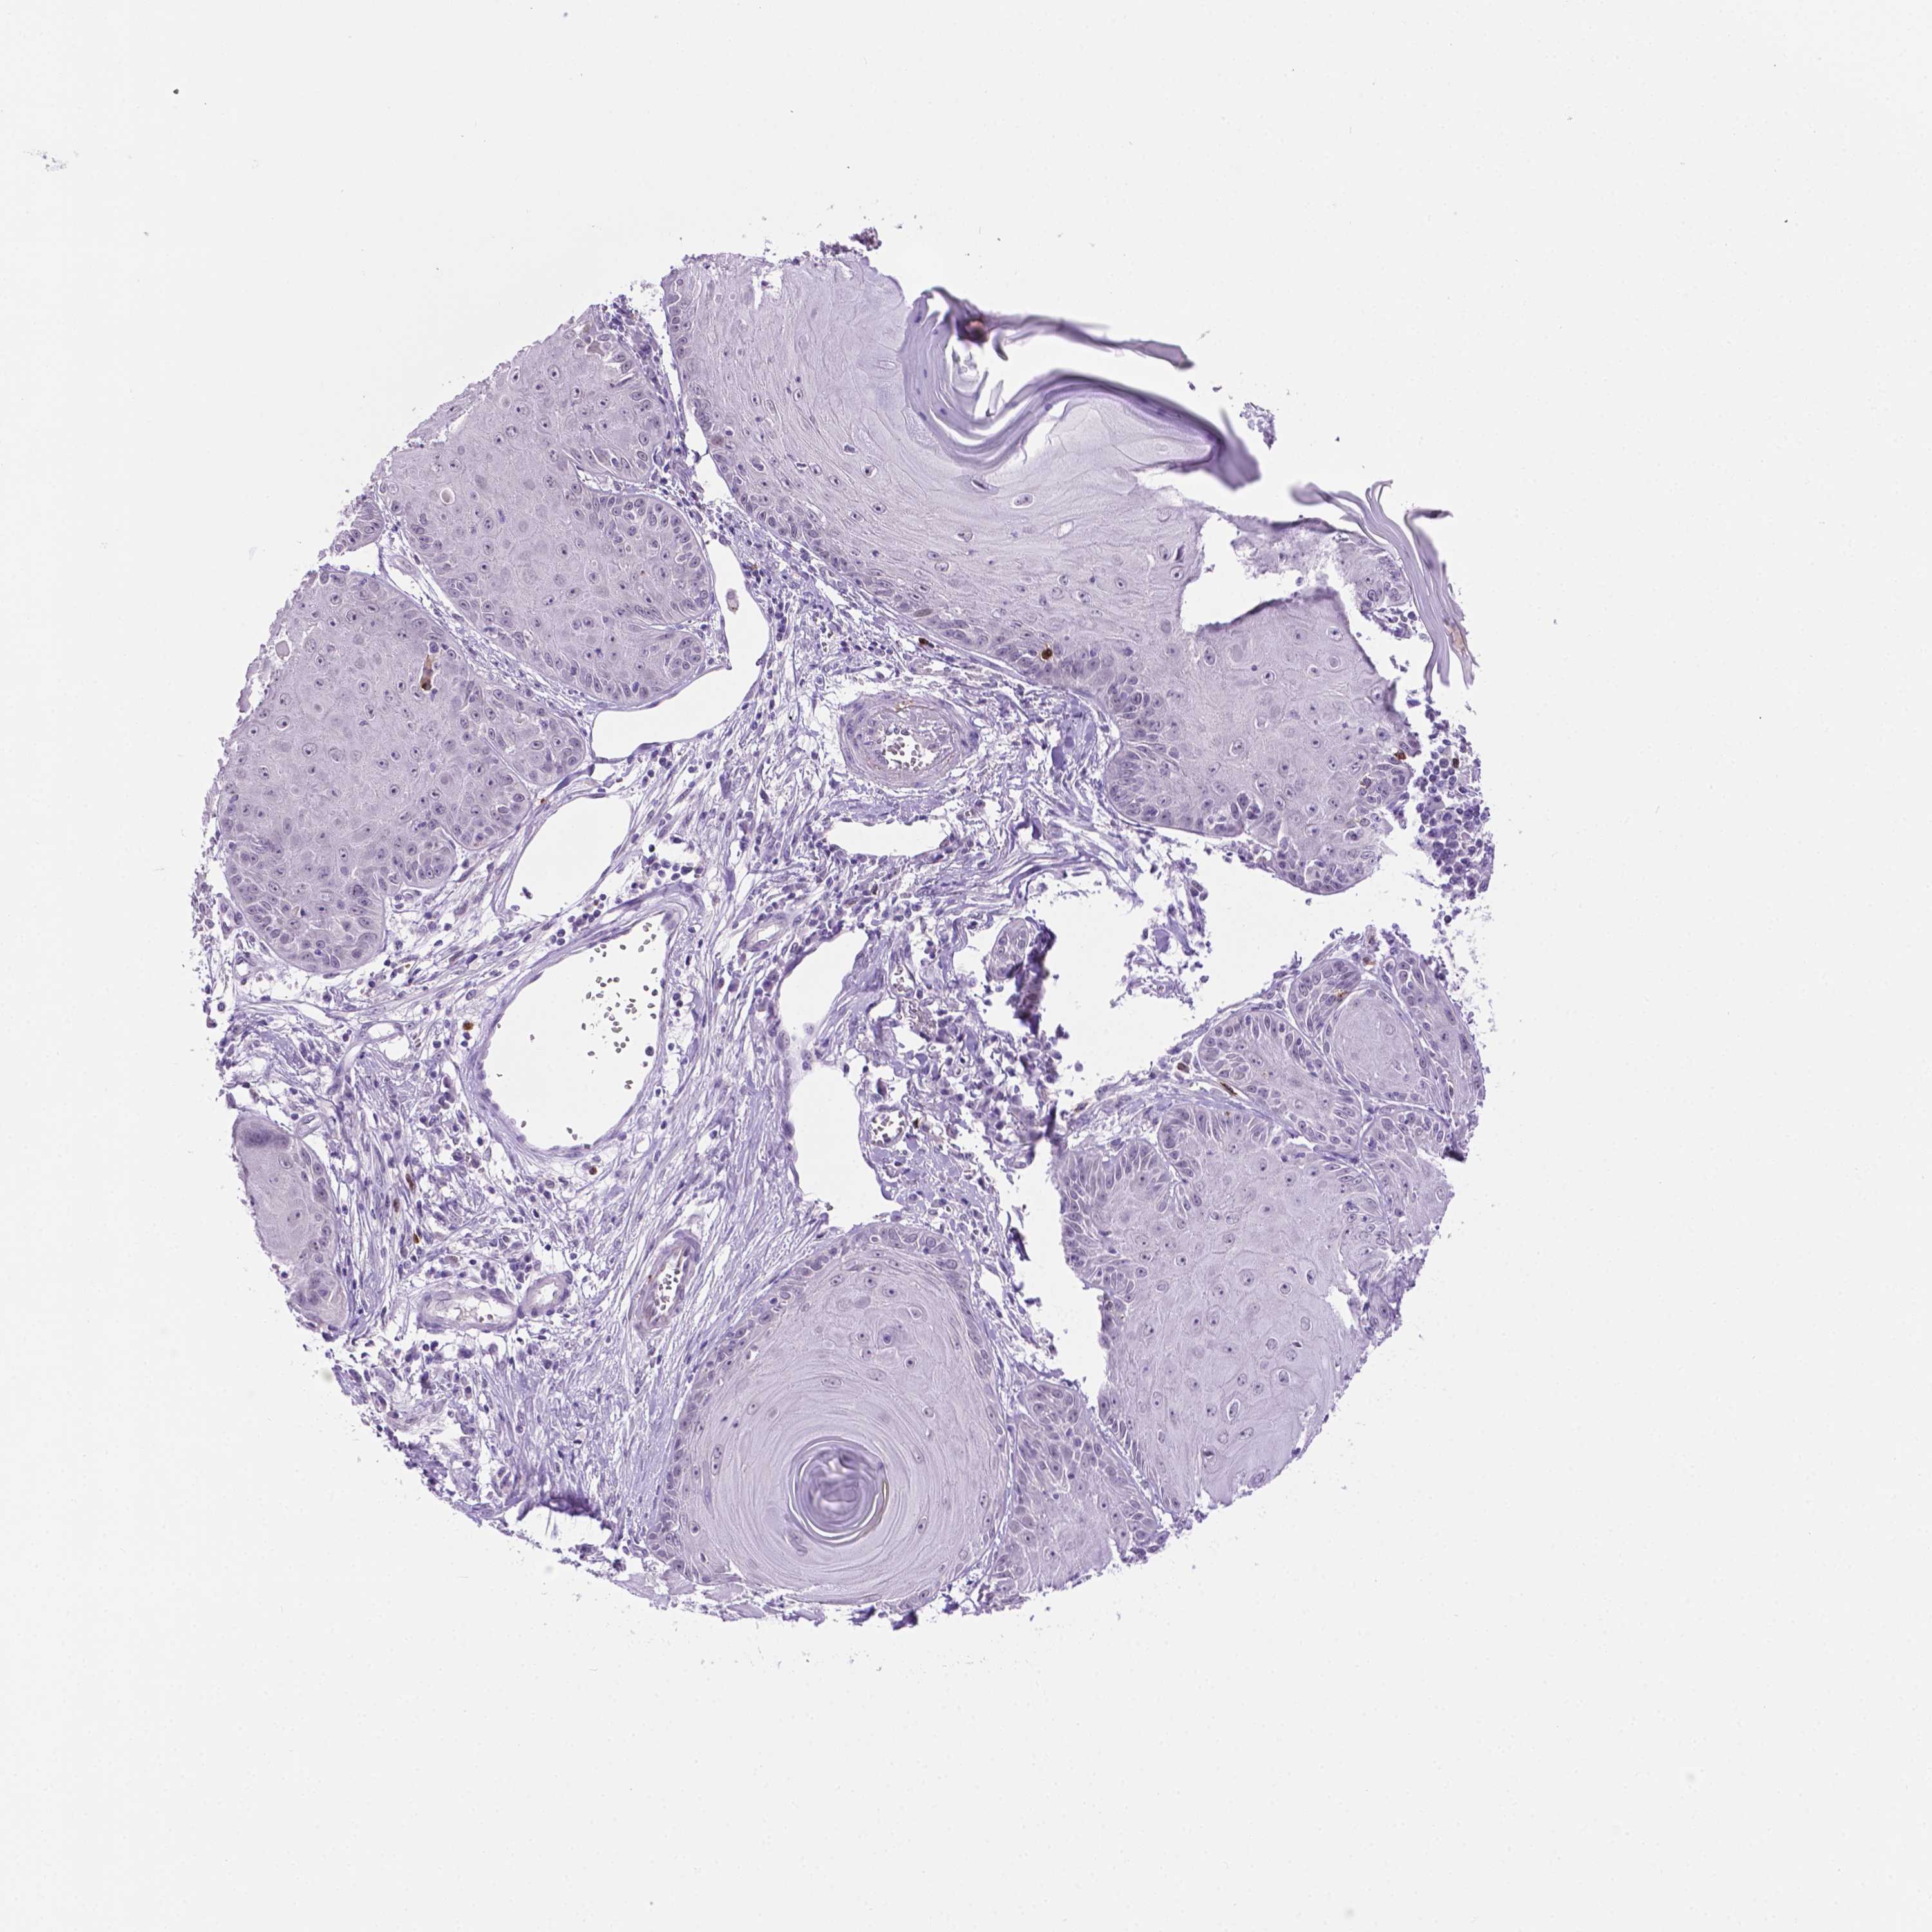

Basal cell and squamous cell cancer

SKIN CANCER - Protein expressioni

A mouse-over function shows sample information and annotation data. Click on an image to view it in a full screen mode. Samples can be filtered based on level of antibody staining by selecting one or several of the following categories: high, medium, low and not detected. The assay and annotation is described here.

Each image is clickable and will lead to virtual microscopy that enables deeper exploration of all samples and also displays staining intensity scores, fraction scores and subcellular localization as well as patient and tissue information for each sample.

Antibody HPA069097

Staining

High

Medium

Low

Not detected

Intensity

Strong

Moderate

Weak

Negative

Quantity

>75%

75%-25%

<25%

None

Location

Nuclear

Cytoplasmic/membranous

Cytoplasmic/membranous,nuclear

Basal cell carcinoma